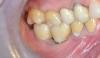

Фотоотчет работы